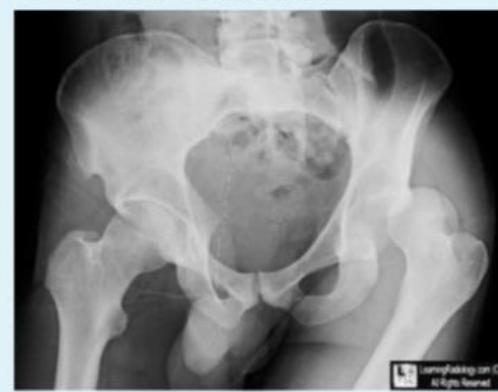

Case B: Pelvic Trauma

4.1) Open Book Fracture Management

1. Diagnosis? Answer: Open book fracture

2. Initial management? Answer: ATLS protocol, pelvic binder application

3. Mention 3 complications: Answer:

- Bleeding

- Pelvic instability

- Neurological injuries

4. Difference between stable and unstable management:

Stable open book fractures can typically be managed non-operatively, with the use of a pelvic binder or external fixation to stabilize the anterior pelvic ring until the injury heals.

Unstable open book fractures require surgical intervention to achieve anatomic reduction and stabilization of both the anterior and posterior pelvic rings.